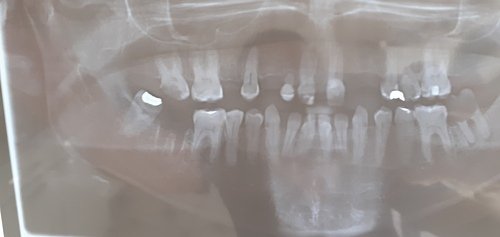

MEU NOME É SILVANA SOU MÃE DA TAMIRES QUE ESTÁ NO VÍDEO . A TAMIRES TEM 29 ANOS E 4 MESES, DEFICIENTE INTELECTUAL E EPILEPSIA , PRECISA DE FAZER IMPLANTE DE PRÓTESE FIXA DEVIDO CRISES CONVULSIVAS. ELA TEM AGENESIA, VÁRIOS DENTES COMPROMETIDOS QUE PRECISA EXTRAIR, ELA DIFICULDADE NA MASTIGAÇÃO, SENTE DOR AO COMER POIS TEM VÁRIOS SENSÍVEIS.